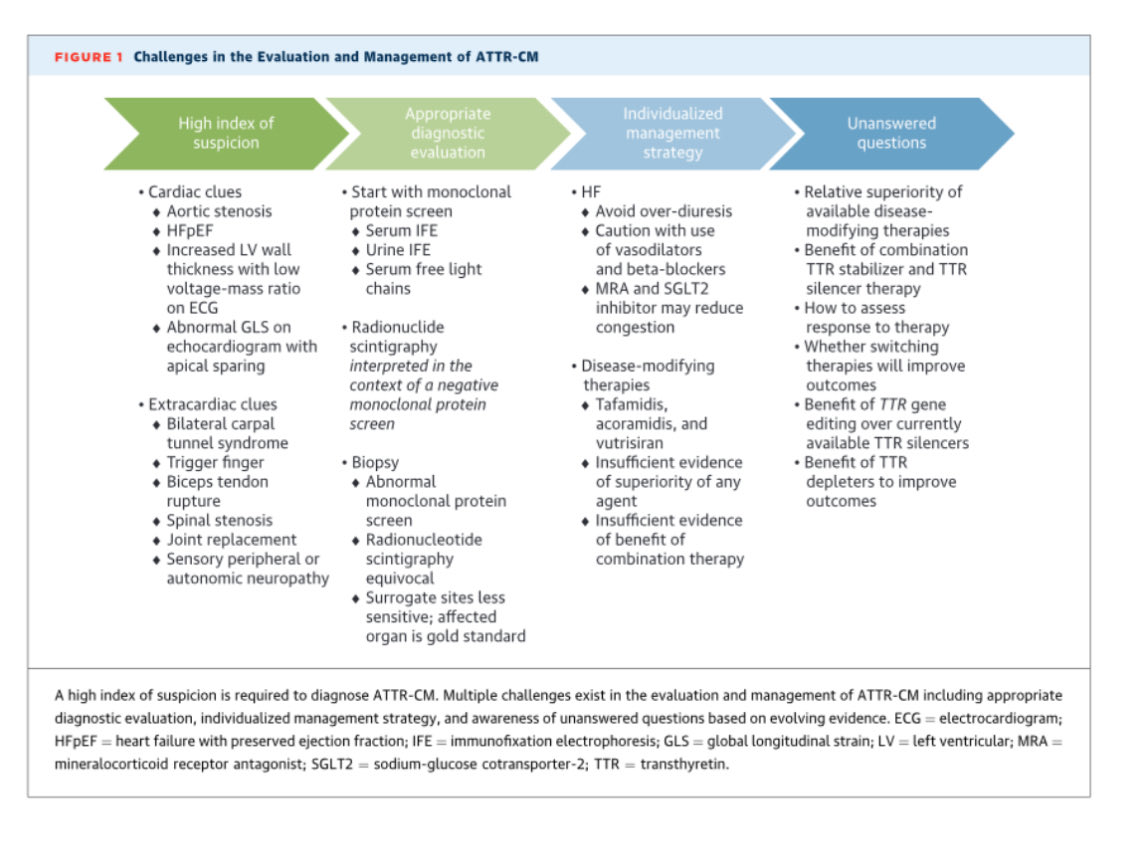

🔴 Transthyretin Cardiac Amyloidosis Evaluation and Management: 2025 ACC Concise Clinical Guidance @JACCJournals #Cardiology #CardioEd #Amyloidosis #FOAMed